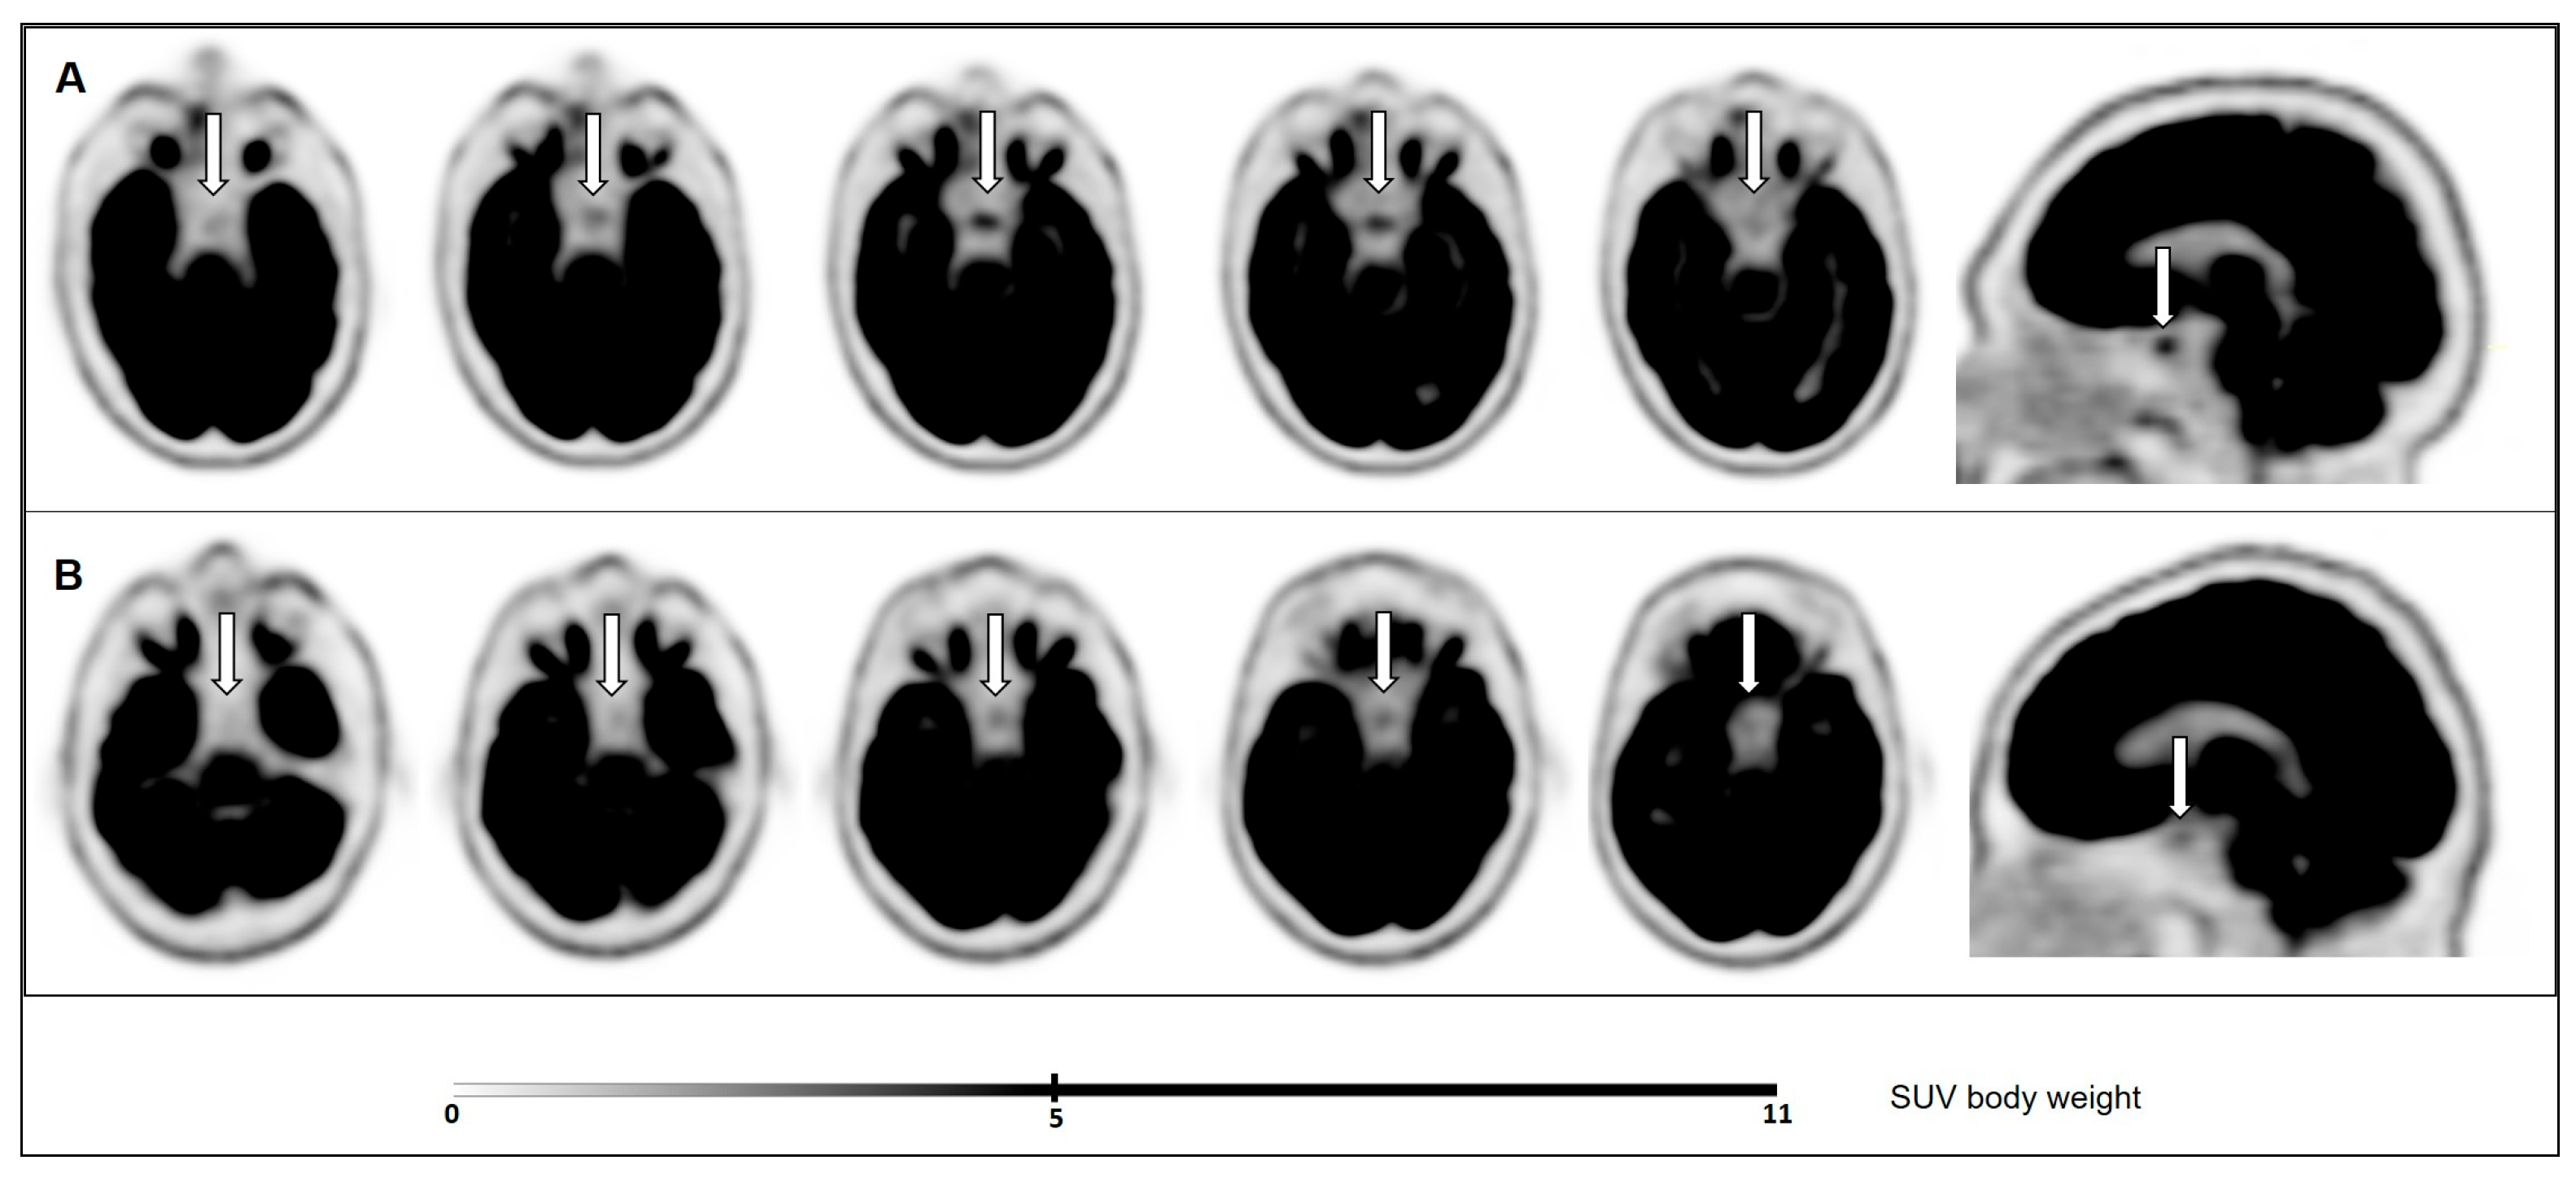

Increased Pituitary Fluorine-18-Fluorodeoxyglucose Uptake in Patients with Differentiated Thyroid Cancer in Hypothyroidism versus under Recombinant Human Thyroid-Stimulating Hormone Stimulation

3.2. Pituitary Metabolic Activity on 18F-FDG PET/CT and Correlation with Serum TSH Levels